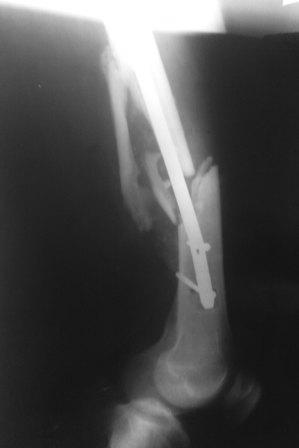

Re: Интрамедуллярный остеосинтез бедра, перелом гвоздя

Большое спасибо за ответы. Прошу прощения, что сразу не показал боковую проекцию (прилагаю сейчас). Может быть с таким торцевым упором не производить динамичсекую фиксацию, а провести динамизацию позже.

Да, такая картина заставляет план подкорректировать. После удаления стержня надо дистрактором одномоментно или, если не получится, постепенно восстановить длину. И для окончательного устранения антекурвации надо взять гвоздь потолще и подлиннее.